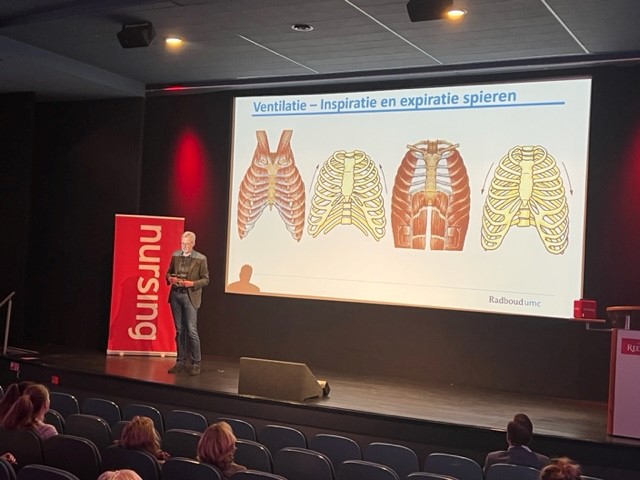

Anatomie & Fysiologie van de longen

Jan Kooloos

Je krijgt in deze openingspresentatie een mooi overzicht van de bouw en werking van de longen. Naast de anatomie, wordt de algemene fysiologie van de longen uitgelicht.

“Kennis van anatomie maakt je beter in je vak”